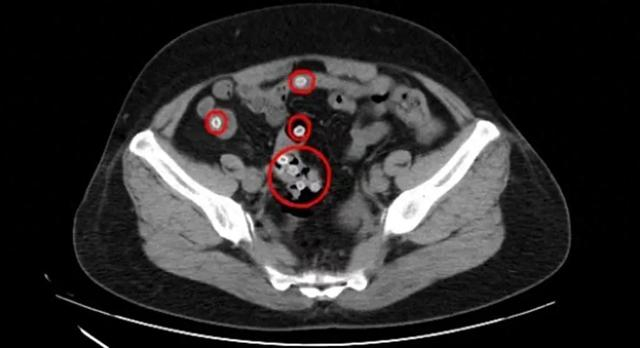

CT影像显示,王阿姨的肠内存在多处类圆形高密度影,密密麻麻的圆圆小白点正是滞留在肠道内的杨梅核,这是导致患者腹痛不止的罪魁祸首。

“这种情况下,患者很有可能会引发胃痉挛和肠梗阻,要尽快将杨梅核排出体外。”谷红苹首先为患者进行解痉止痛治疗,然后为其开具了通便的药物促杨梅核排出。在药物的帮助下,王阿姨成功在第二天完成排便,肠道内的杨梅核也顺利排出体外。